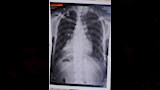

لم يكن صيف أسيوط الحارق هو وحده ما يلهب صدر هذا الرجل الأربعيني الذي وصل إلى مستشفى القلب الجامعي، فهناك قلبٌ لديه يسكن في غير مكانه، اختار يمين صدره، في حالة نادرة تُعرف بـ "انقلاب وضع الأحشاء الكلي".

وصل الرجل وقد أنهكه ضيق التنفس وأثقلته آلام الصدر، حاملًا بين ضلوعه لغزًا تشريحيًا لا يحدث إلا مرة بين كل عشرات الآلاف. لكن الفحوصات الدقيقة كشفت عن تحدٍ أكبر من مجرد قلبٍ مهاجر؛ فالروماتيزم كان قد نخر صماماته، وتسبب في ضيق حاد بالصمام الميترالي، وارتجاع خطير في الصمام الأورطي، بينما تشبثت جلطة خطيرة بالأذين الأيسر، محولةً حالته النادرة إلى سباق معقد ضد الزمن.